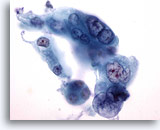

Figure 87

Bronchial wash

This cluster contains many abnormal cells. Their nuclear detail is seen at the periphery of the cluster. 20x

Bronchial wash

This cluster contains many abnormal cells. Their nuclear detail is seen at the periphery of the cluster. 20x

Figure 87

Bronchial wash

This cluster contains many abnormal cells. Their nuclear detail is seen at the periphery of the cluster.

20x

Bronchial wash

This cluster contains many abnormal cells. Their nuclear detail is seen at the periphery of the cluster.

20x